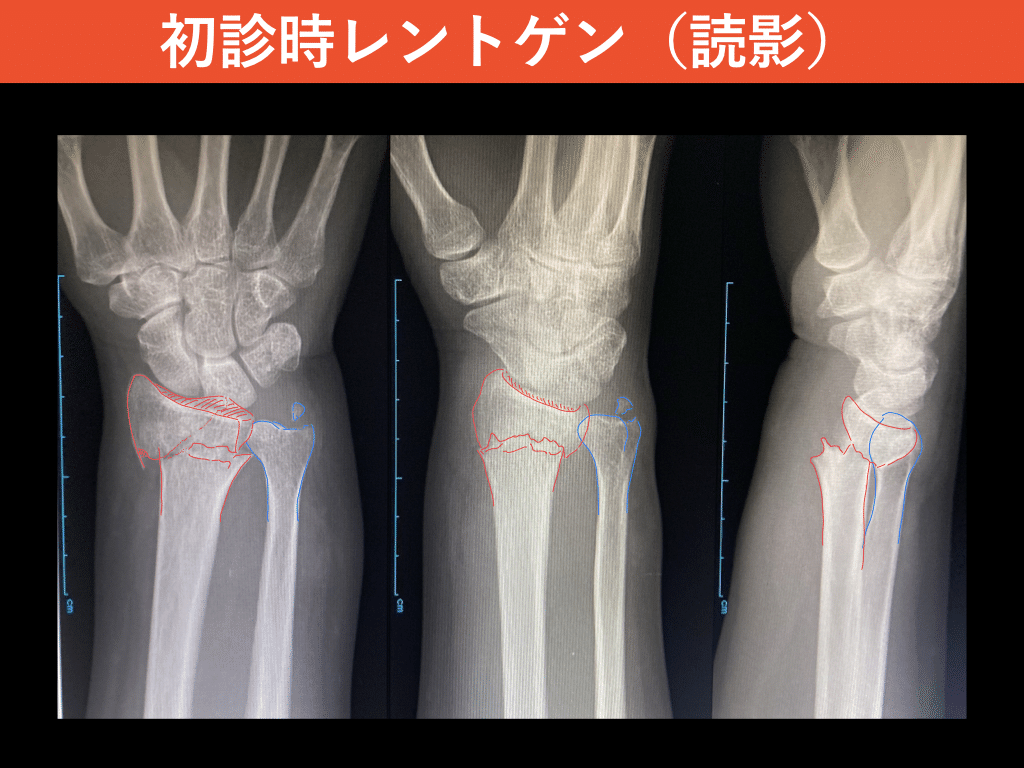

• 症例報告:橈骨遠位端骨折(AO分類:C2)」#書く習慣152|整形外科で

• 今回は中学生男子:橈骨遠位端骨折(転移あり) 病院でレントゲン検査